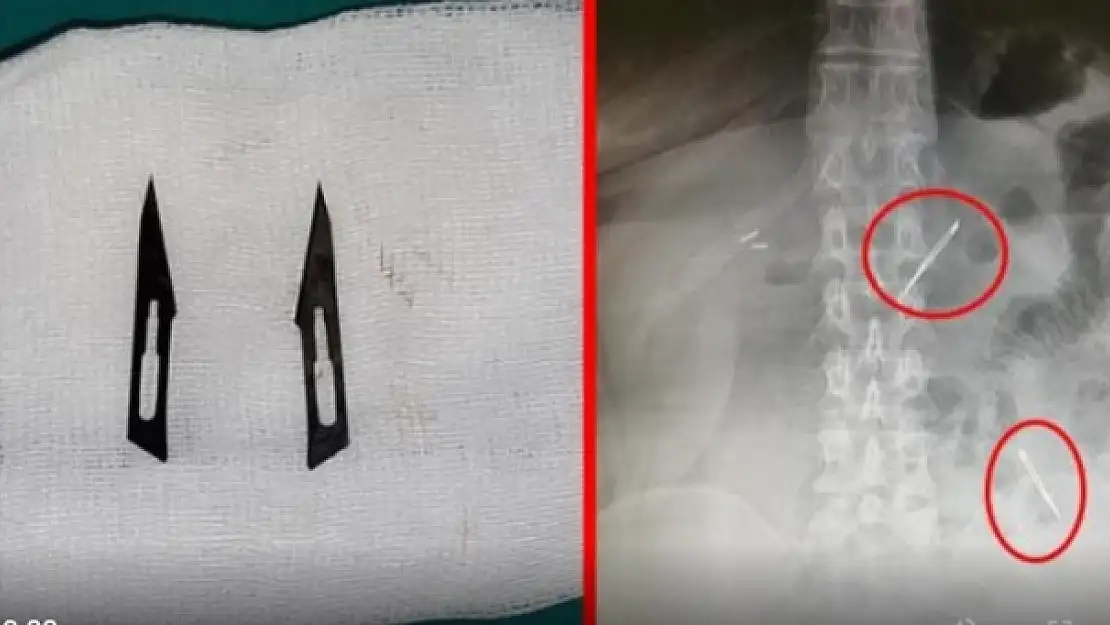

Sağlık Bilimleri Üniversitesi Ankara Atatürk Sanatoryum Eğitim ve Araştırma Hastanesi'ne mide ve karın bölgesinde aşırı ağrı şikayeti ile müracaat eden 46 yaşındaki D.E.'nin yapılan tahlil, tetkik ve çeşitli görüntülemelerden sonra bağırsak kısmında 2 adet neşter olduğu tespit edildi. Genel cerrahi kliniği tarafından zorlu bir ameliyat sonrasında neşterler kadının vücudundan çıkarıldı. 46 yaşındaki D.E. neşterleri nasıl yuttuğunu bilmediğini tahminen ekmek ile birlikte yutabilmiş olabileceğini ifade etti. Ameliyatı gerçekleştiren Sağlık Bilimleri Üniversitesi Ankara Atatürk Sanatoryum Eğitim ve Araştırma Hastanesi Genel Cerrahi Kliniği Eğitim ve İdari sorumlusu Prof. Dr. Hakan Buluş ise hastanın yoğun şikayetleri üzerine çektikleri röntgen sonrasında 2 adet neşteri görünce şaşkına uğradıklarını söyledi.

Hastanın şikayetlerinin artması üzerine gerçekleştirilen tetkiklerde 46 yaşındaki kadının karın bölgesinde 2 adet yabancı cisim olduğunu tespit ettiklerini, detaylı inceleme sonucunda bu cisimlerin neşter olduğunu fark ettiklerini belirten Prof. Dr. Buluş, "Yaklaşık 10 gün önce kliniğimize karın ağrısı ve bulantı şikayetleri ile başvurdu. Bizim yaptığımız fiziki muayene ve tetkiklerinde hastanın direkt karın grafisinde 2 adet yabancı cisim olduğunu tespit ettik. Aslında yabancı cisim bizim güncel grafiğimizde sık karşılaştığımız bir durum değil, fakat nadir de olsa görebildiğimiz bir patoloji.

Biz de bunun üzerine ayrıntılı değerlendirmeler ve tetkikler yaptık. Sonrasında 2 adet yabancı cismin bistüri (neşter) ile uyumlu olduğunu gördük. Bunun üzerine hastanın şikayetlerinin de artması üzerine, ameliyat kararı verdik. Yaptığımız ameliyatta ince bağırsağın yaklaşık 180'inci santimetresinde bu yabancı cisimlerin olduğunu tespit ettik. Bunun üzerine ameliyatla bunları çıkarttık. Hastamızın sağlık durumu şuan gayet iyi. Ameliyattan sonraki üçüncü günü. Şuan bir problemi yok, inşallah birkaç gün içerisinde şifa ile taburcu etmeyi düşünüyoruz" şeklinde konuştu.

Çıkardıkları cismin, neşterin normalde ameliyatlarda kullanılan bir malzeme olduğunu söyleyen Prof. Dr. Buluş, "Çıkardığımız yabancı cisimler bizim ameliyatlarda sıkça kullandığımız 11 numara dediğimiz bir bistüri tipi. Ebatları da yaklaşık 4 santime yarım santim ebatlarında. Ucunun sivri olması nedeniyle ince bağırsak mukozasına saplanarak enflamasyon ve bir karın ağrısı yapması, sonrasında da ağrı şikayetlerinin artmasına neden olmasından dolayı ameliyat kararı verdik" diye konuştu.